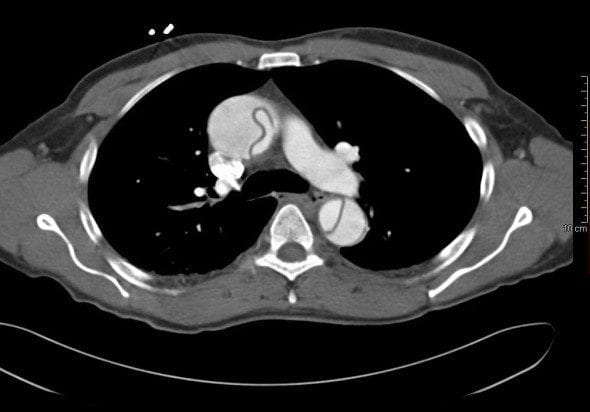

The patient proceeds to a CTA chest.

The CTA chest reveals the presence of a thoracic aortic dissection